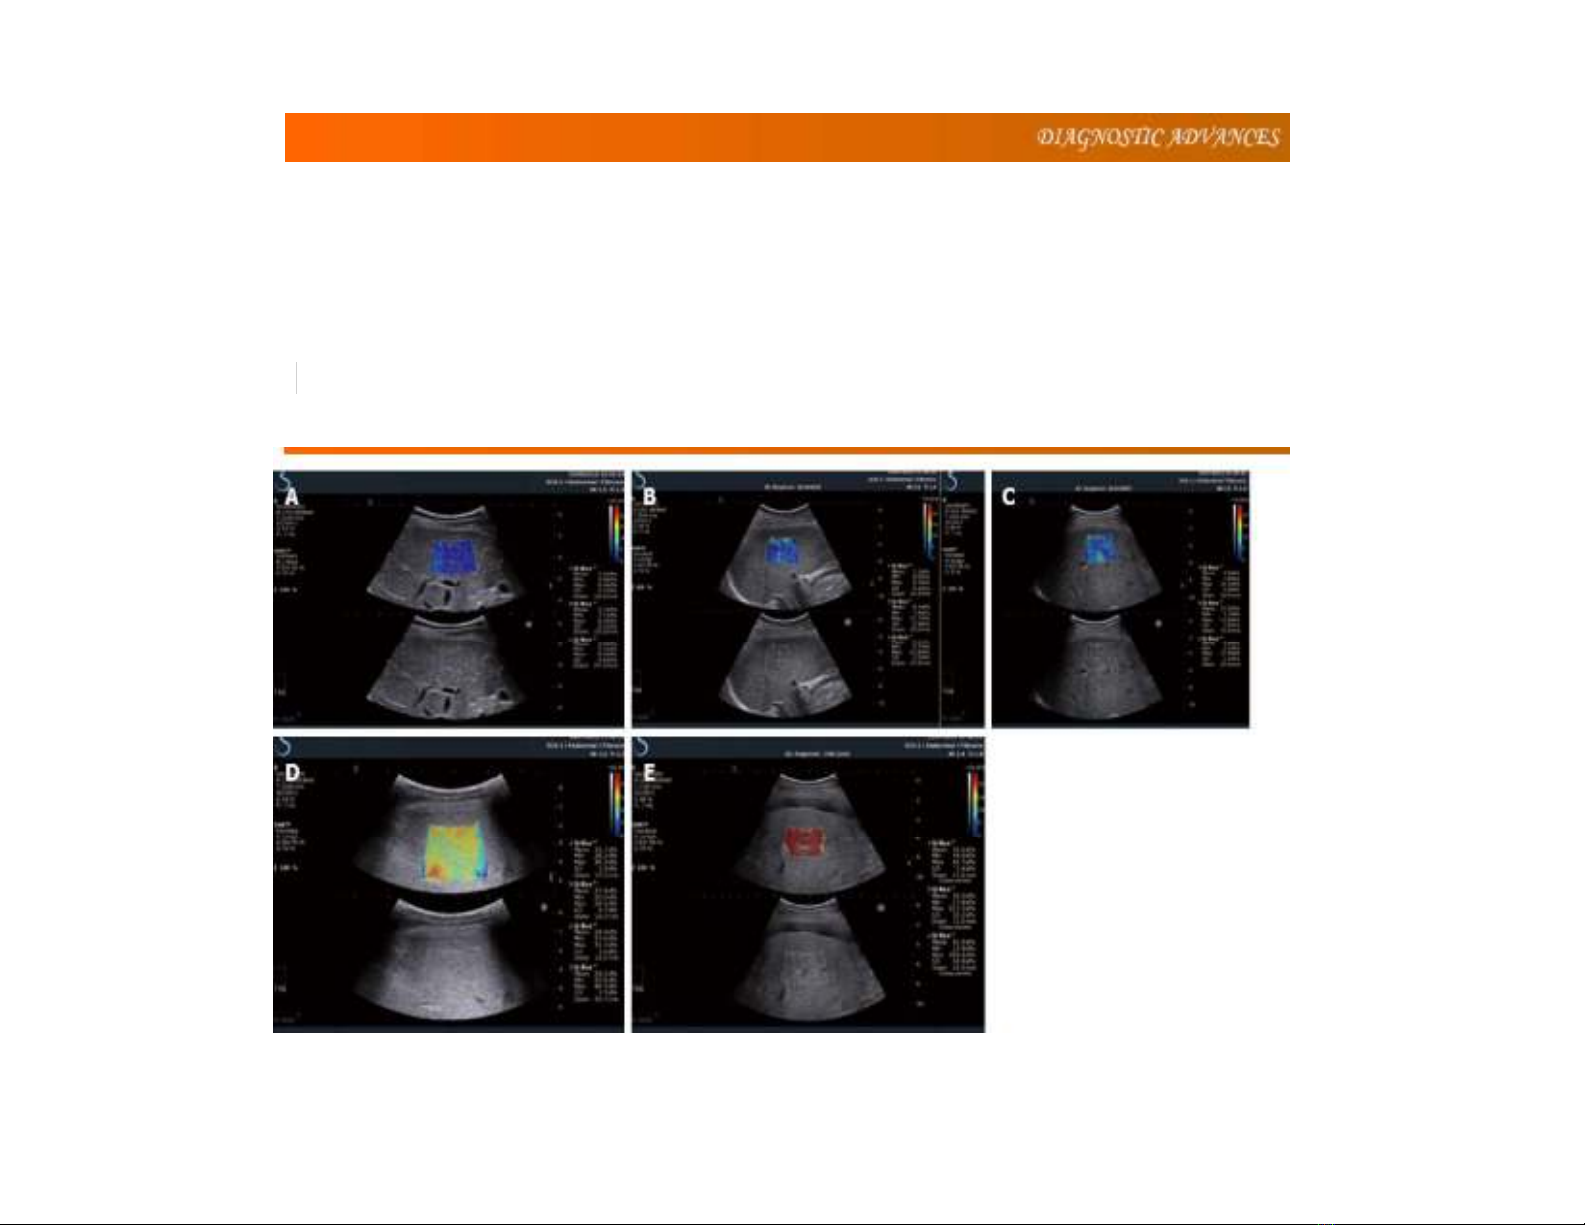

Siêuâmđànhồigan, bình luậnvề hướngdẫnsiêu

âmđànhồi củaEFSUMB 2013

Xiin-Wu Cui, Mireen Friedrich-Rust, Chiara De Molo, Andre Ignee, Dagmar Schreiber-Dietrich,

Christoph FDietrich